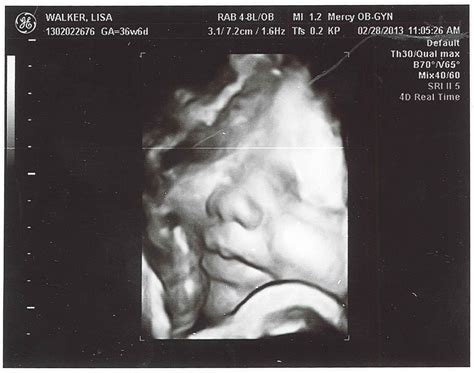

Welcoming a new life into the world is an extraordinary experience, and understanding the developmental milestones of a 37-week newborn can help parents navigate this exciting journey with confidence. At 37 weeks, babies are considered early term, and while they are generally healthy, they may still require some special care compared to full-term infants. This post will delve into the key aspects of a 37-week newborn, including their physical characteristics, developmental milestones, and essential care tips.

• Size and Weight: At 37 weeks, babies usually weigh between 5 pounds 8 ounces (2.5 kg) and 6 pounds 2 ounces (2.8 kg). Their length can range from 18 to 20 inches (45.7 to 50.8 cm).

• Appearance: The skin may be wrinkled and translucent, and the baby might have a fine hair called lanugo covering their body. The head may appear disproportionately large compared to the body.